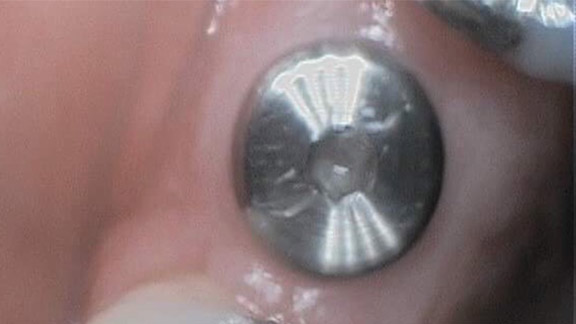

Patient Has Dental Crown Placed

This patient had a crown on #12 done by Dr Gentner along with adding it to fit their partial - Great work

Dental Crown

Dental Crown

Restored Filling With Crown

New crown on this back tooth! Looks amazing!